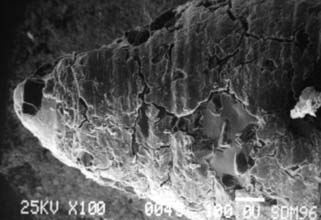

Fig. 7-6 Scanning electron micrographs of a rotary instrument. A, Unused diamond. B, Unused carbide. C, Worn diamond. D, Diamond particles have fractured at the level of the binder.

(Courtesy of Dr. J. L. Sandrik.)